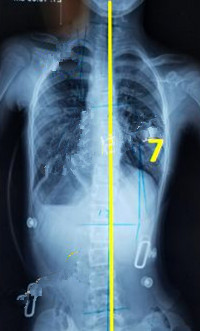

一般經(jīng)過三個月至六個月的治療,對稱度都能得到改善,力線回正。

此時由于患者已經(jīng)完全適應(yīng)支具的力點,且體表變化較大,為了進一步矯正,我們需要對支具進行調(diào)整。如果由于孩子身高的變化較大,為了更進一步的矯正,可以考慮更換新的支具。

穿支具后